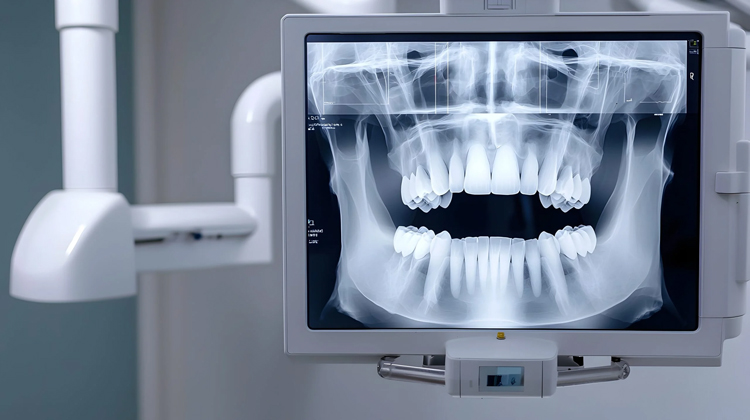

What is 3D Tomography?

3D tomography is one of the most advanced imaging methods used in dentistry. Unlike traditional X-rays, it provides a three-dimensional view of the teeth, jaw, and facial structure. This allows even the finest details to be seen, ensuring highly accurate treatment planning. It offers significant advantages, particularly in implant surgery, jaw joint disorders, and the positioning of impacted teeth.